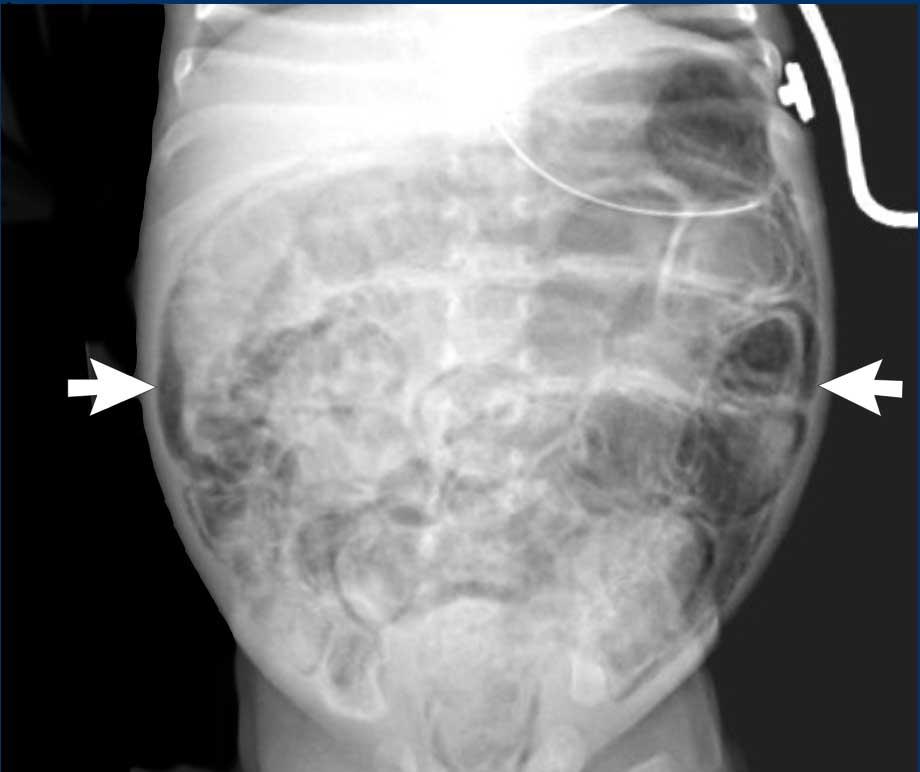

Hình ảnh

X-quang bụng cho thấy các quai ruột giãn và phân bố hơi không đều với vùng thiếu hơi ở góc phần tư dưới phải.

Phân bố hơi trong lòng ruột

Trên X-quang, cần đánh giá phân bố hơi trong lòng ruột.

Phân bố hơi trong ruột

Cần đánh giá sự phân bố hơi trong ruột, vì các vùng thiếu hơi khu trú có thể đại diện cho đoạn ruột bệnh lý.

Do góc phần tư dưới phải là vị trí thường bị tổn thương nhất, đây cũng là vùng thường xuyên nhất có biểu hiện vắng mặt hơi ruột.